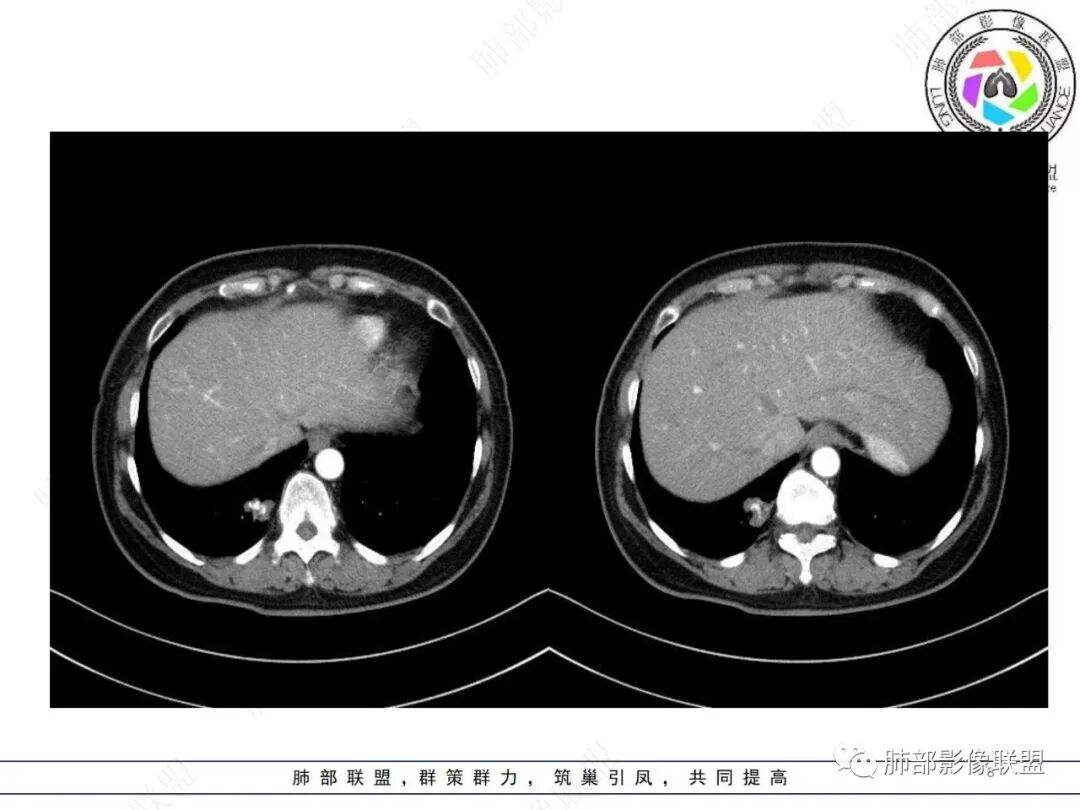

中年女性 右肺下叶不规则实性病灶中心伴钙化,边缘有分叶、胸膜线样牵拉,增强后中等强化,常规思路考虑良性病灶,但是如果有老片 持续观察这个病灶 是否是在增大,腺癌还是可能的,有的肺癌可伴发钙化就是密度没有这么高,疤痕基础上发生也有可能。

CT强化值应该是大于20HU 轻中度强化

从强化程度来看,强化不支持错构瘤,病灶有膨胀性有收缩及脐样改变,不能排除肺癌(腺癌)

这个形态还是像腺癌,有膨隆有分叶,边缘磨玻璃边界清,非钙化部分轻度强化。腺癌可以钙化的,估计是干扰项

右肺下叶分叶状实性结节伴钙化,胸膜牵拉似有侵犯,增强后轻度强化,倾向恶性,腺癌可能。

右肺下叶内基底段胸膜下分叶状肿块,边界清,密度不均匀,有成簇状钙化(与错构瘤钙化不同),实性部分有强化,肿块边缘凹陷明显(有收缩力),周围集血管束特点,方向首选肺肿瘤,考虑肺腺Ca。